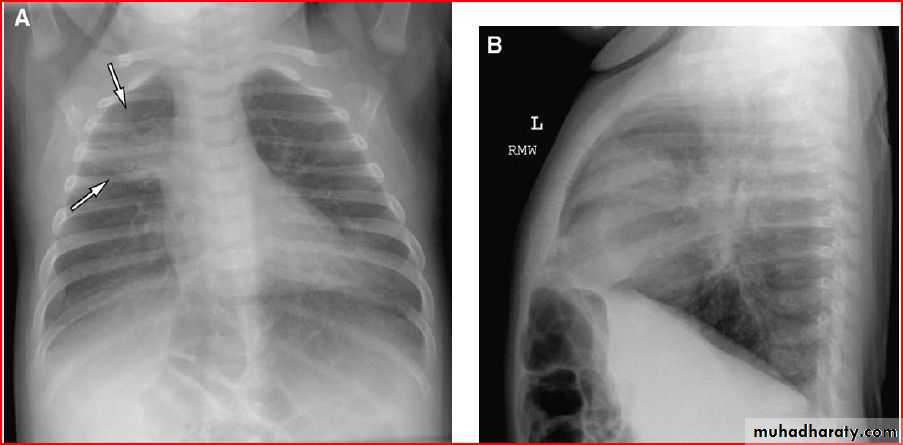

3 month infant presented with cough & dyspnea

Xray shows hyperinflated chest (depresed diaphragm , > 6 ribsMay be bronchiolitis

Hyperinflated chest

Hx of FB

A showing normal x rayB xray during expiration showing lt. lung emphysema make shifting of mediastinum